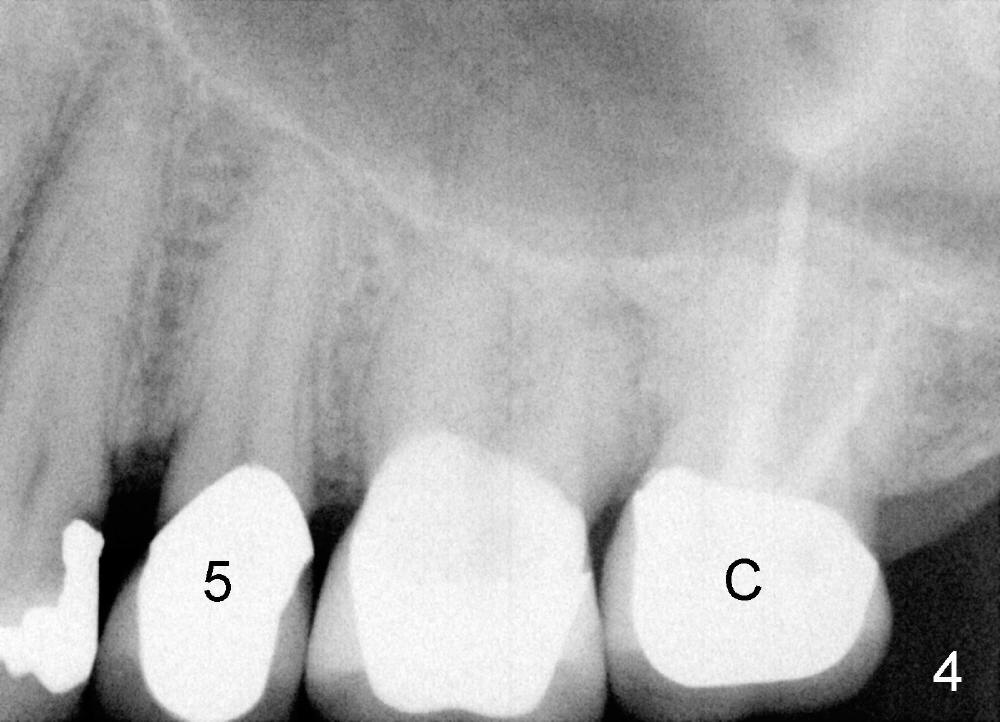

陈先生五十来岁,牙齿不好,右上有一个三个单位桥(图一:5-7),右下四个单位桥(5-8)。五年前他第一次来诊所时左上7有牙髓炎症状(图二),那颗牙齿有很大银汞充填物(A),之下出现龋齿(*)。出于救死护伤精神,开始做根管治疗(图三:*牙胶尖),当时他原来牙医出差了,之后给左上7戴上牙冠(图四:C)。其实图四X光片拍摄是在左上7根管治疗之后一年半,这次左上5有牙髓炎症状,再次为他做根管治疗(图五:*)。他又很久才回来:两年半,这次问题更严重:左上7断了(图五),好在他毫无怨言,可能与他是修理工有关,牙齿也需要修修补补。他也知道现在必须做植牙,这时我们非常自豪告诉他我们能做植牙,他便回家凑钱。一年半后他又从天降,左上问题还没有解决,右下8基牙在桥下出现龋齿(图六:^),必须拔除,这时右下6,7必须先做植牙(图六:植牙设计;N:下齿槽神经; L:颏神经襻(loop))。末端缺牙做活动义齿效果不好,据研究表明它只能恢复百分之十咀嚼功能,而植牙百分之百。